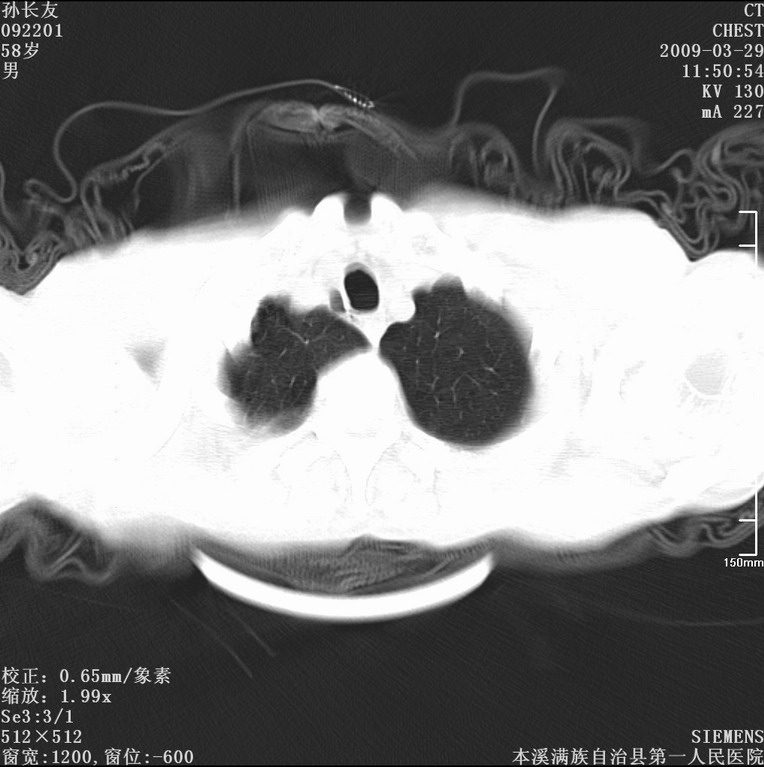

以下是引用liaoqiang在2009-3-30 8:29:00的发言:[br]所上传的层面示气管未见确切异常。